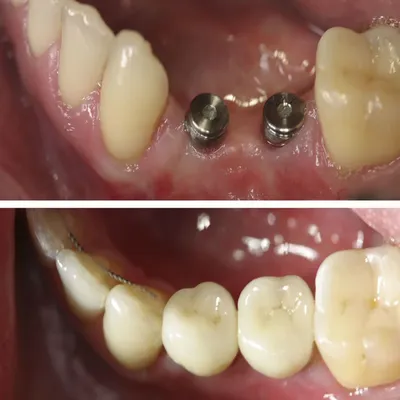

پایه فلزی در لثه برای بازسازی دندان از دست رفته

نصب اباتمنت و تاج نهایی (ماه ۳–۶)

در پایان، اباتمنت بهعنوان رابط روی فیکسچر نصب شده و تاج دندانی قرار میگیرد. این بخش ظاهر لبخند را بازسازی میکند و توانایی جویدن و صحبتکردن طبیعی را به بیمار بازمیگرداند.

نمای نزدیک از پیچ فلزی داخل بافت لثه

قبل و بعد بازسازی فک بالا با دندانهای جدید و طبیعی

تغییر چشمگیر لبخند پس از ترمیم کامل و اصلاح طرح لبخند

نمای واقعی از پایه فلزی کاشت و پروتز ثابت روی لثه